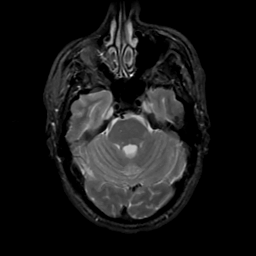

MR Study #4, March 3, 1991 -- Slice #14

[Home][Help][Clinical][Tour 1][Tour 2] Slice 14